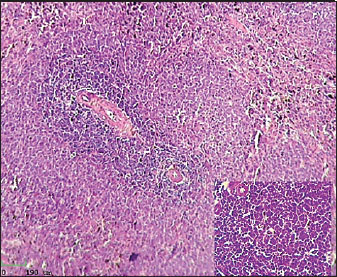

Histological analysis of spleen

Histological examination of the splenic tissue of rats treated with L-arginine showed notable pathological alterations. These included: Congestion of blood vessels within both the red and white pulp and lymphoid hyperplasia in the white pulp, indicating increased proliferation of lymphoid cells, suggestive of immune stimulation or chronic inflammation (Fig. 4). In contrast, the spleen from control male rats exhibited normal histological architecture. The white pulp and red pulp regions were clearly distinguishable. Central arteries and blood vessels appeared unremarkable, and no signs of congestion, inflammation, or hyperplasia were observed. The lymphoid follicles within the white pulp were of normal size and density (Fig. 3)

Fig. 3. Histological section of male rat spleen of control group, stained with Hematoxylin and Eosin (H&E), showing villus structure at 10x magnification using light microscopy.

Fig. 4. Histological section of male rat spleen treated with L-arginine, stained with Hematoxylin and Eosin (H&E), showing villus structure at 10x magnification using light microscopy.